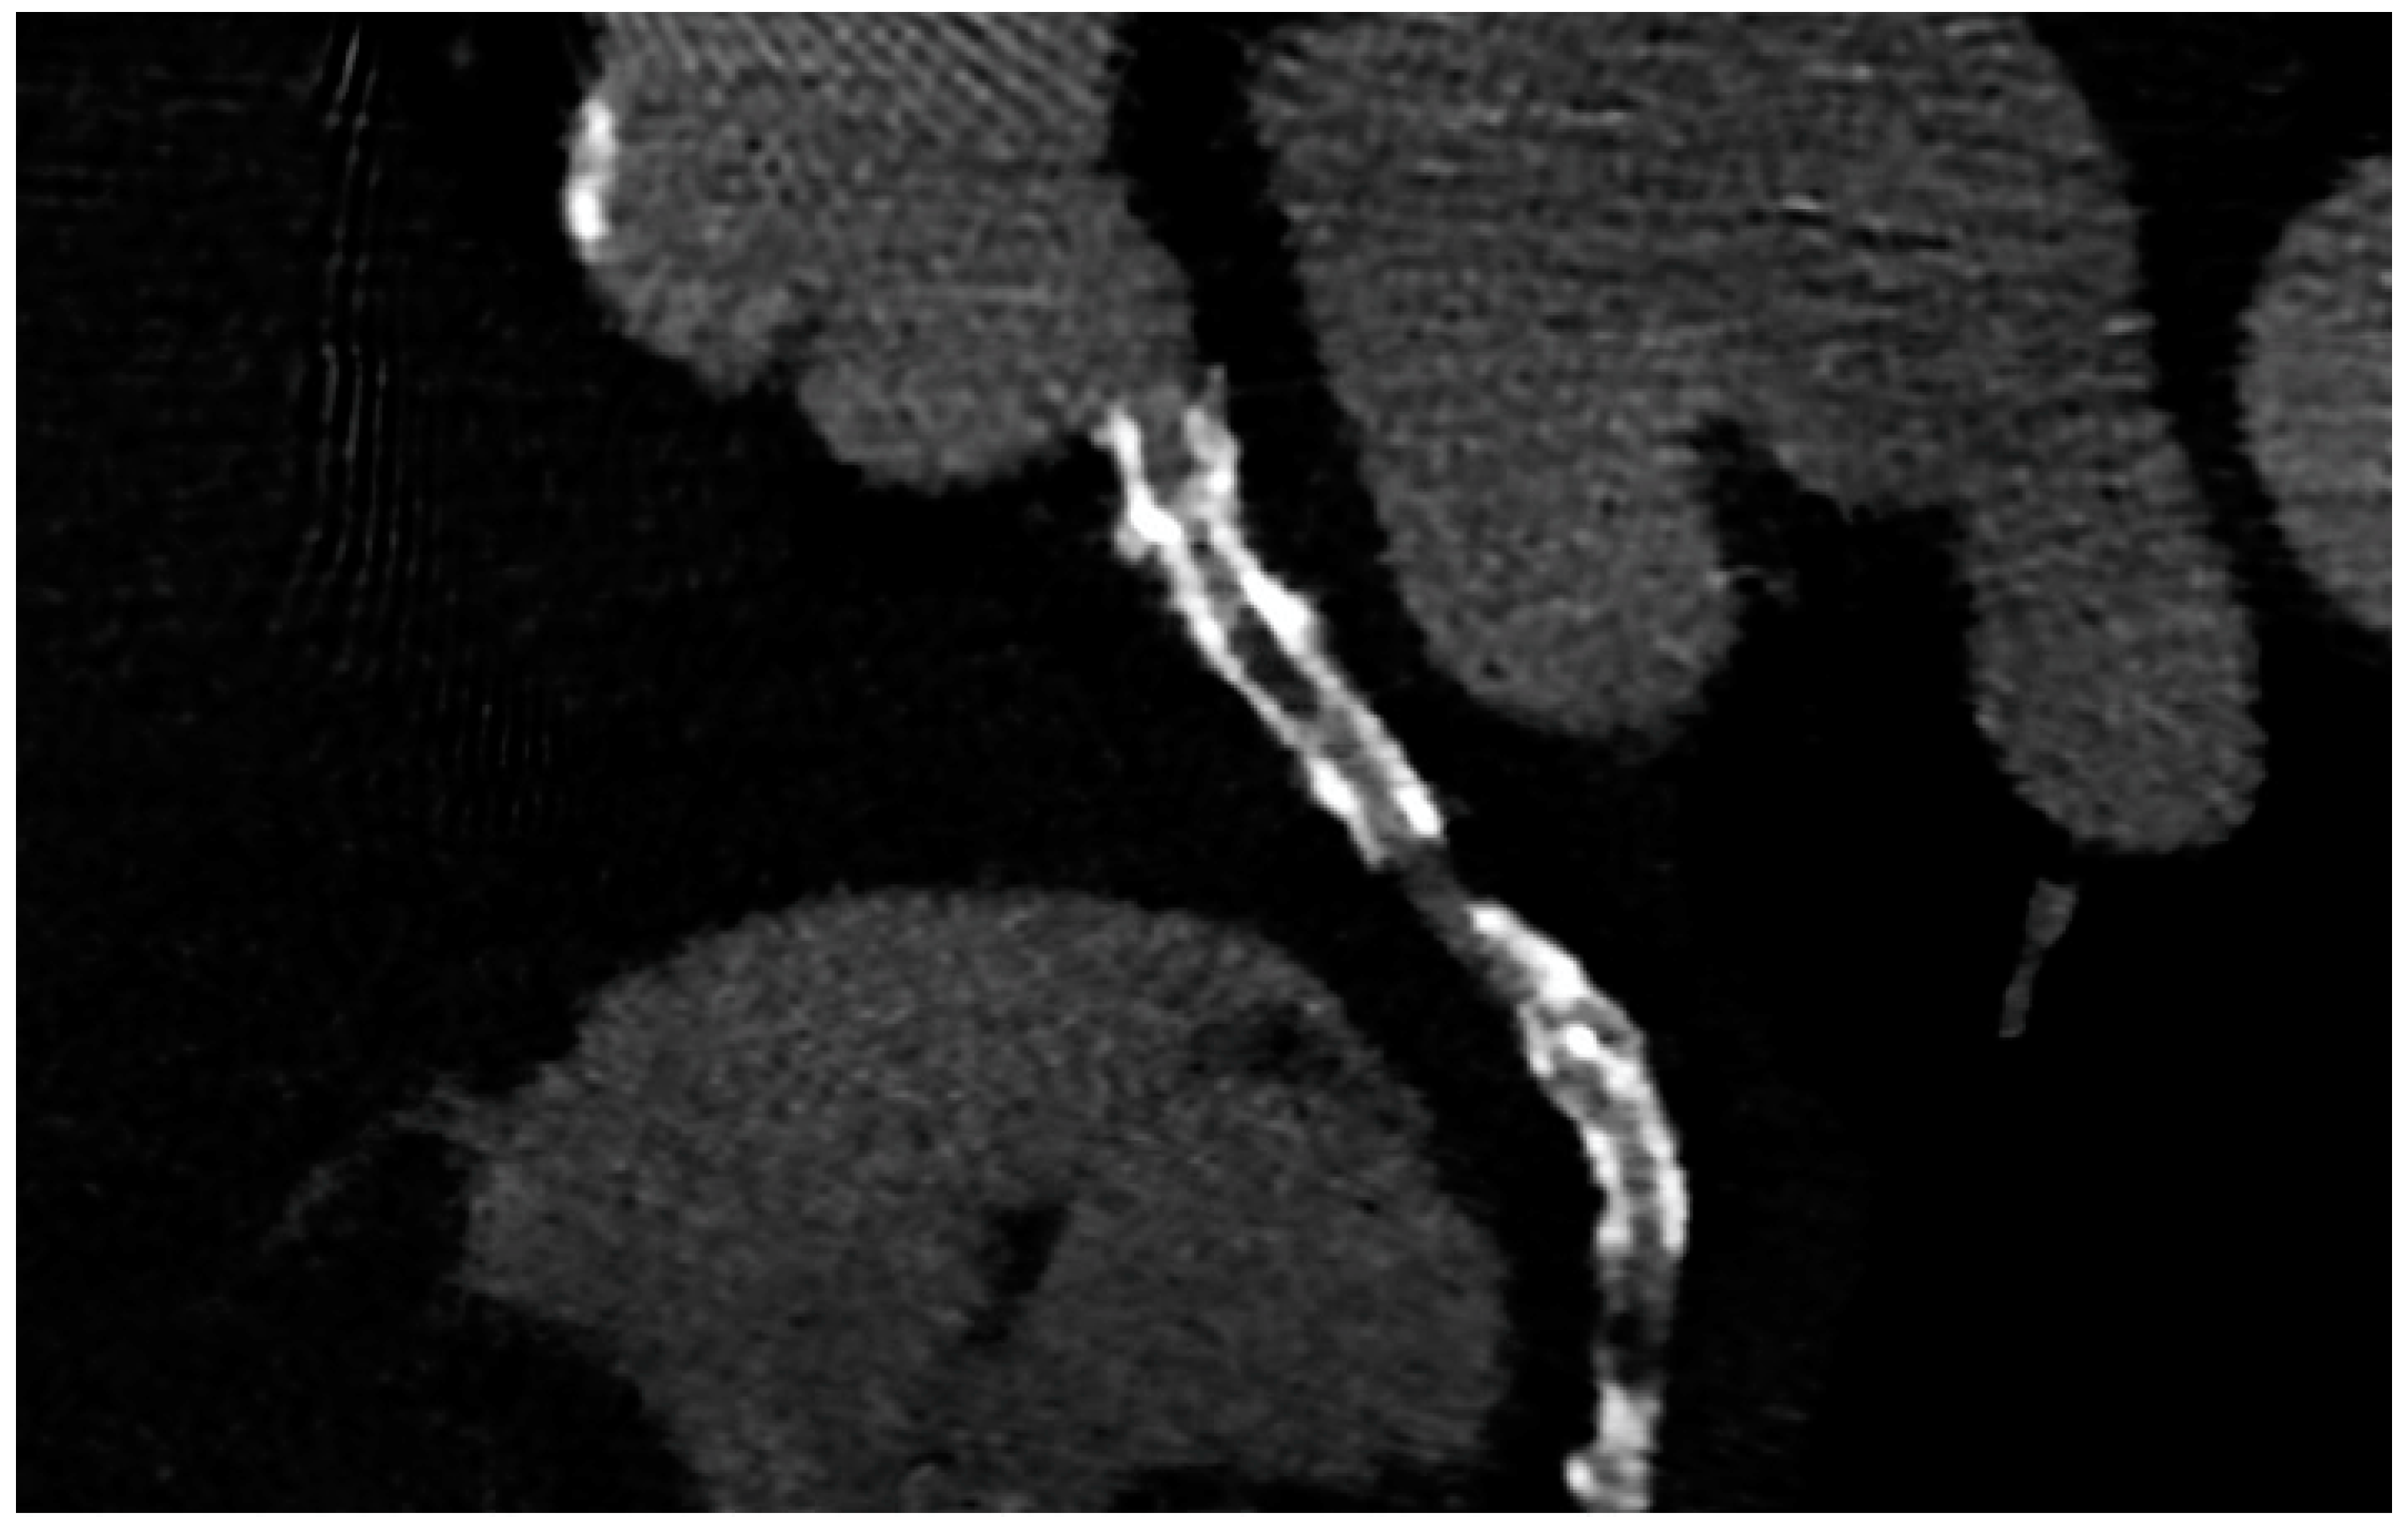

Figure 2.

ISR in a stent previously implanted in the proximal segment of the left circumflex artery.